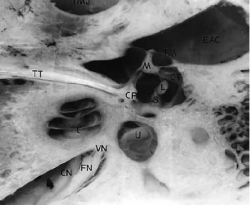

FN – facial nerve (სახის ნერვი)

TT – tensor tympani (აპკის დამჭიმავი)

C – cochlea (ლოკოკინა)

U – utriculus (უტრიკულუსი)

CN – cochlear nerve (კოხლეარული ნერვი)

VN – vestibular nerve (ვესტიბულარული ნერვი)

CP – cochleariform process (კოხლეარული მორჩი)

M – maleus neck (ჩაქუჩის ყელი)

L – long process of incus (გრდემლის გრძელი მორჩი)

S – stapes (უზანგი)

TM – tympanic membrane (დაფის აპკი)

EAC – external auditory canal (გარეთა სასმენი მილი)

TMJ – temporo mandibular joint (ყბის სახსარი)